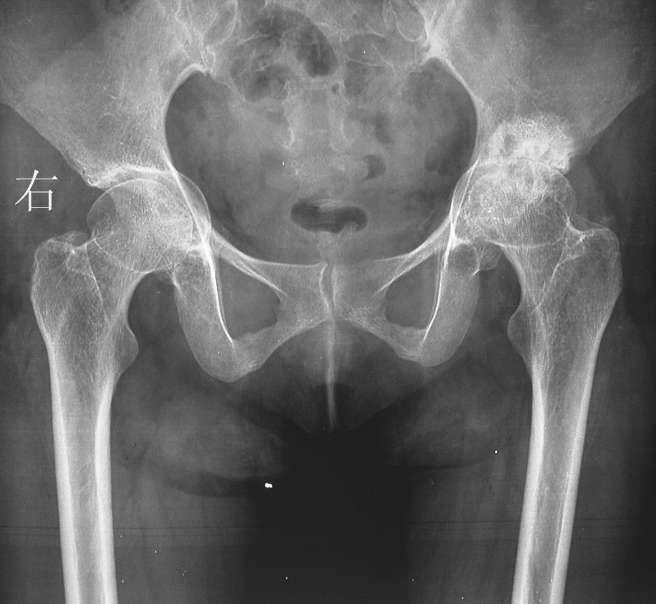

女性34岁,左髋疼痛5年,伴有背部疼痛,腰部活动受限,局部有压痛。

腰椎、左侧骶髂关节及双侧髋关节间隙变窄,左侧明显且有软骨下局部骨硬化,首先考虑强制性脊柱炎,鉴别包括类风湿性关节炎、沙门氏菌骨关节感染及布氏菌骨关节感染等。

脊柱改变支持as,需查hla-b27及结合临床。骨盆为奥托氏骨盆,左侧股骨头无菌性坏死继发关节退变可能。

腰椎、左侧骶髂关节及双侧髋关节间隙变窄,左侧明显且有软骨下局部骨硬化,首先考虑强制性脊柱炎.

单从骨盆片来看的话确实应该怀疑类风湿 这个和otto骨盆有点像